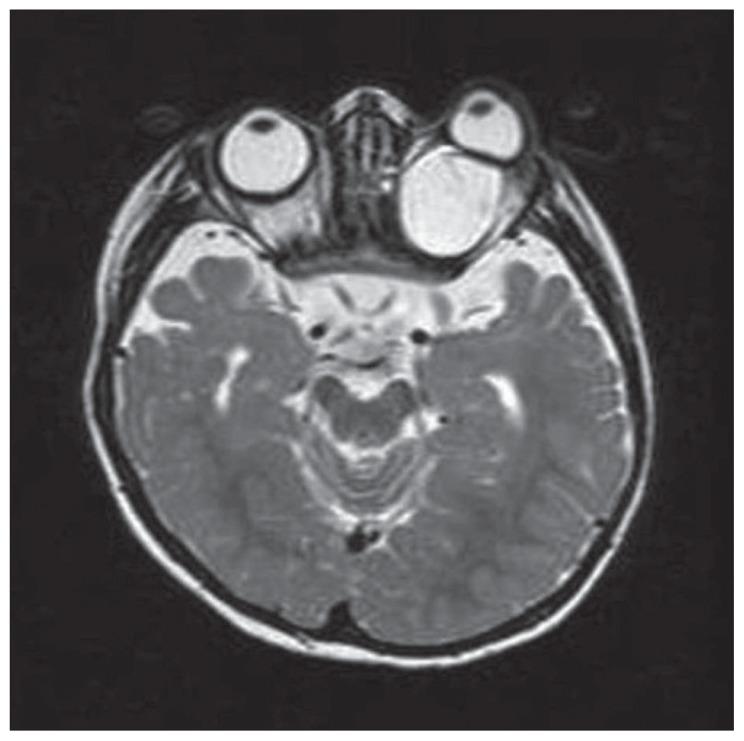

Aicardi syndrome (AS) is an X-linked inherited disorder characterized by infantile spasms, chorioretinal lacunae, and agenesis or hypogenesis of the corpus callosum. The syndrome is more frequently seen in females but is observed in XXY male patients. Central nervous system, ocular, and costovertebral malformations may also seen in AS. Eye findings are of a considerable diagnostic importance; the chorioretinal lacunae are pathognomonic for AS and are generally bilateral. The outcome of the disease is generally severe, with a high mortality rate and poor developmental outcome. It is not clear which characteristics of the syndrome are related to a good prognosis in terms of psychomotor development, epileptic seizures, and survival. The purpose of this report was to demonstrate the spectrum of the clinical findings and the course of AS in two Turkish patients with different ocular and cranial MRI findings.

艾卡迪综合征(AS)是一种X连锁遗传性疾病,其特征为婴儿痉挛、脉络膜视网膜缺损以及胼胝体发育不全或发育不良。该综合征在女性中更为常见,但在XXY男性患者中也有发现。中枢神经系统、眼部和肋椎畸形在AS中也可能出现。眼部表现具有相当重要的诊断意义;脉络膜视网膜缺损是AS的特征性表现,通常为双侧性。该病的预后通常较差,死亡率高且发育结局不佳。目前尚不清楚该综合征的哪些特征与精神运动发育、癫痫发作和生存方面的良好预后相关。本报告的目的是展示两名土耳其患者的临床发现谱以及AS的病程,这两名患者具有不同的眼部和头颅MRI表现。